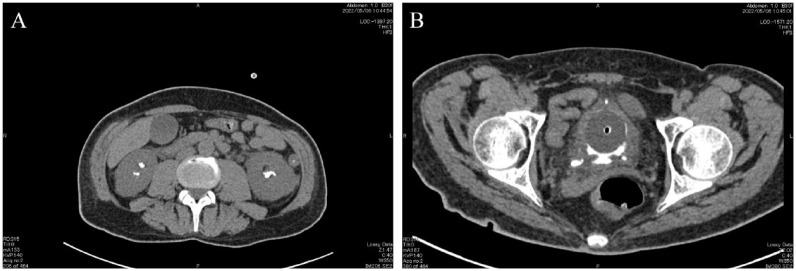

Fungal bezoar formation is a complication of fungal urinary tract infections that are usually caused by Candida species and other fungal types. They can form in any site along the urinary tract and may cause an obstruction to the urine flow that would require drainage by nephrostomy, a ureteric stent, and sometimes surgical intervention is needed. In this case report we discuss a case of an adult male who had an extensive fungal bezoar infection caused by Candida tropicalis causing him anuria and acute kidney injury. The bezoars were found in the bladder, the ureters, and both kidneys. The patient was treated with bilateral ureteric stent insertion and with fluconazole for 3 weeks. Bilateral ureteroscopy and urine culture were done after 2 months and they showed that the bezoars have been eradicated on both gross and microscopic levels.